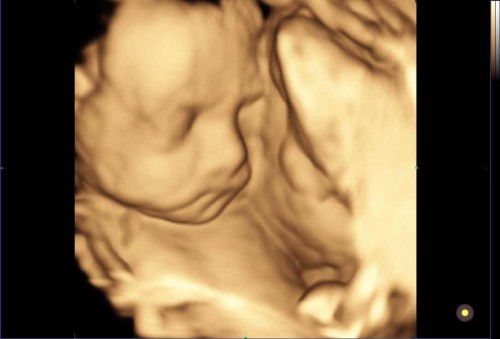

จมูกโด่งงง